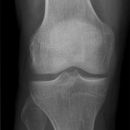

Kniegelenk

Kniegelenk a.p.

Patient in Rückenlage, Bein gestreckt und leicht nach innen gedreht, so dass die Kondylen parallel zur Tischebene liegen, bei schlankem Bein leichte Unterpolsterung des Gelenkes.

Senkrecht auf Gelenkspalt, d.h. unterer Patellarand.

Häufiger Fehler: Gelenkspalt nicht frei projiziert, durch zu starke Außenrotation bzw. zu starke Innenrotation.

Kniegelenkspalt muss frei abgebildet sein, Tibiaplateau muss strichförmig dargestellt werden, medial leicht oval, Kniescheibe mittelständig.